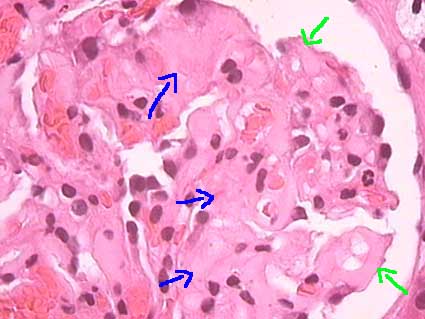

Glomeruli are affected in almost all the cases of AA amyloidosis and in less than half of AL amyloidosis. The aspect is similar in both diseases. Deposits can be nodular or irregular in mesangium. In some cases there are deposits predominantly in mesangium (usually in earlier phases) and in others they are equally extensive in mesangium and glomerular capillary walls; usually they are more prominent surrounding the vascular pole (Figures 1, 2 and 3). Distribution of the changes can be irregular in a glomerulus and among glomeruli, but in long-standing disease deposits are usually more homogenously distributed. When the deposits are ample in mesangium, without formation of nodules, and involving the entire glomerulus, they adopt a pattern called mesangial diffuse. In capillary walls they can be subendothelial and/or subepithelial. In this last location they tend to form spikes perpendicular to the GBM giving a membranous GN aspect (Figure 4); I have had the opportunity to see a pair of cases initially misinterpreted like this GN; a careful histologic evaluation of mesangium and arterioles will allow us to arrive to the correct diagnosis and to carry out Congo red stain to confirm it. In advanced lesions there is a global replace of the tuft, with glomerulosclerosis appearance; nevertheless these glomeruli appear greater and Congo red positive; long time after, these deposits tend to disappear leaving only sclerosis. Usually there is no cellular proliferation. In cases with little glomerular involvement diagnosis can be difficult and requires high suspicion to request Congo red and/or electron microscopy.

Figure 1. Amorphous, eosinophilic deposits in mesangium (blue arrows) and capillary walls (green arrows) that give a solidified aspect to the tuft (H&E, X400).